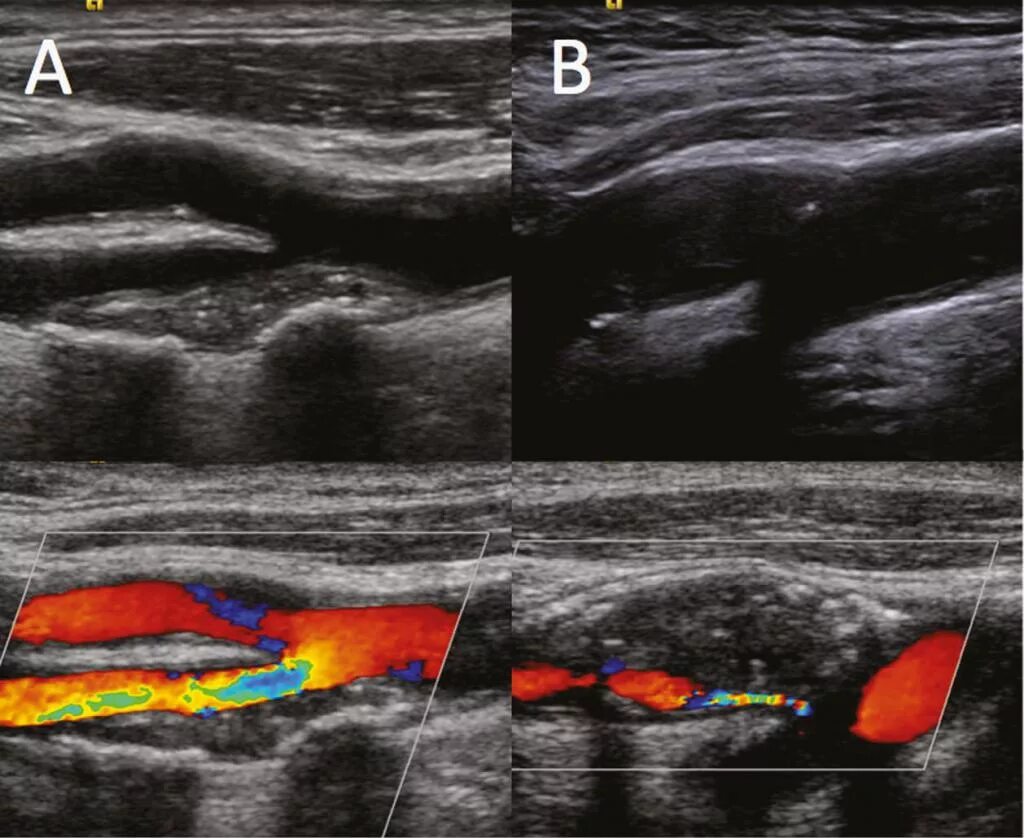

Филлеры на узи